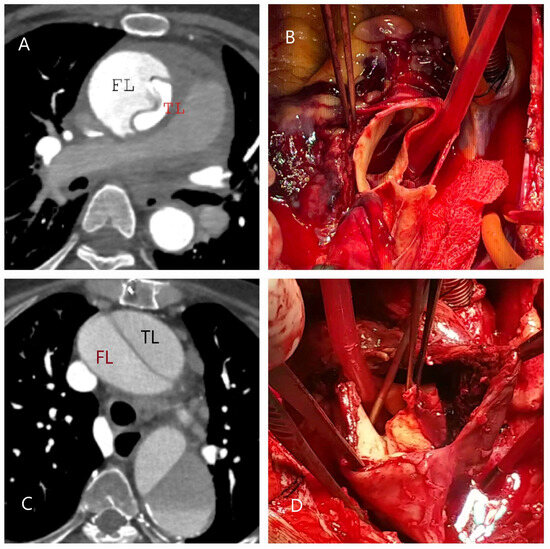

5.2.3. Computed Tomography